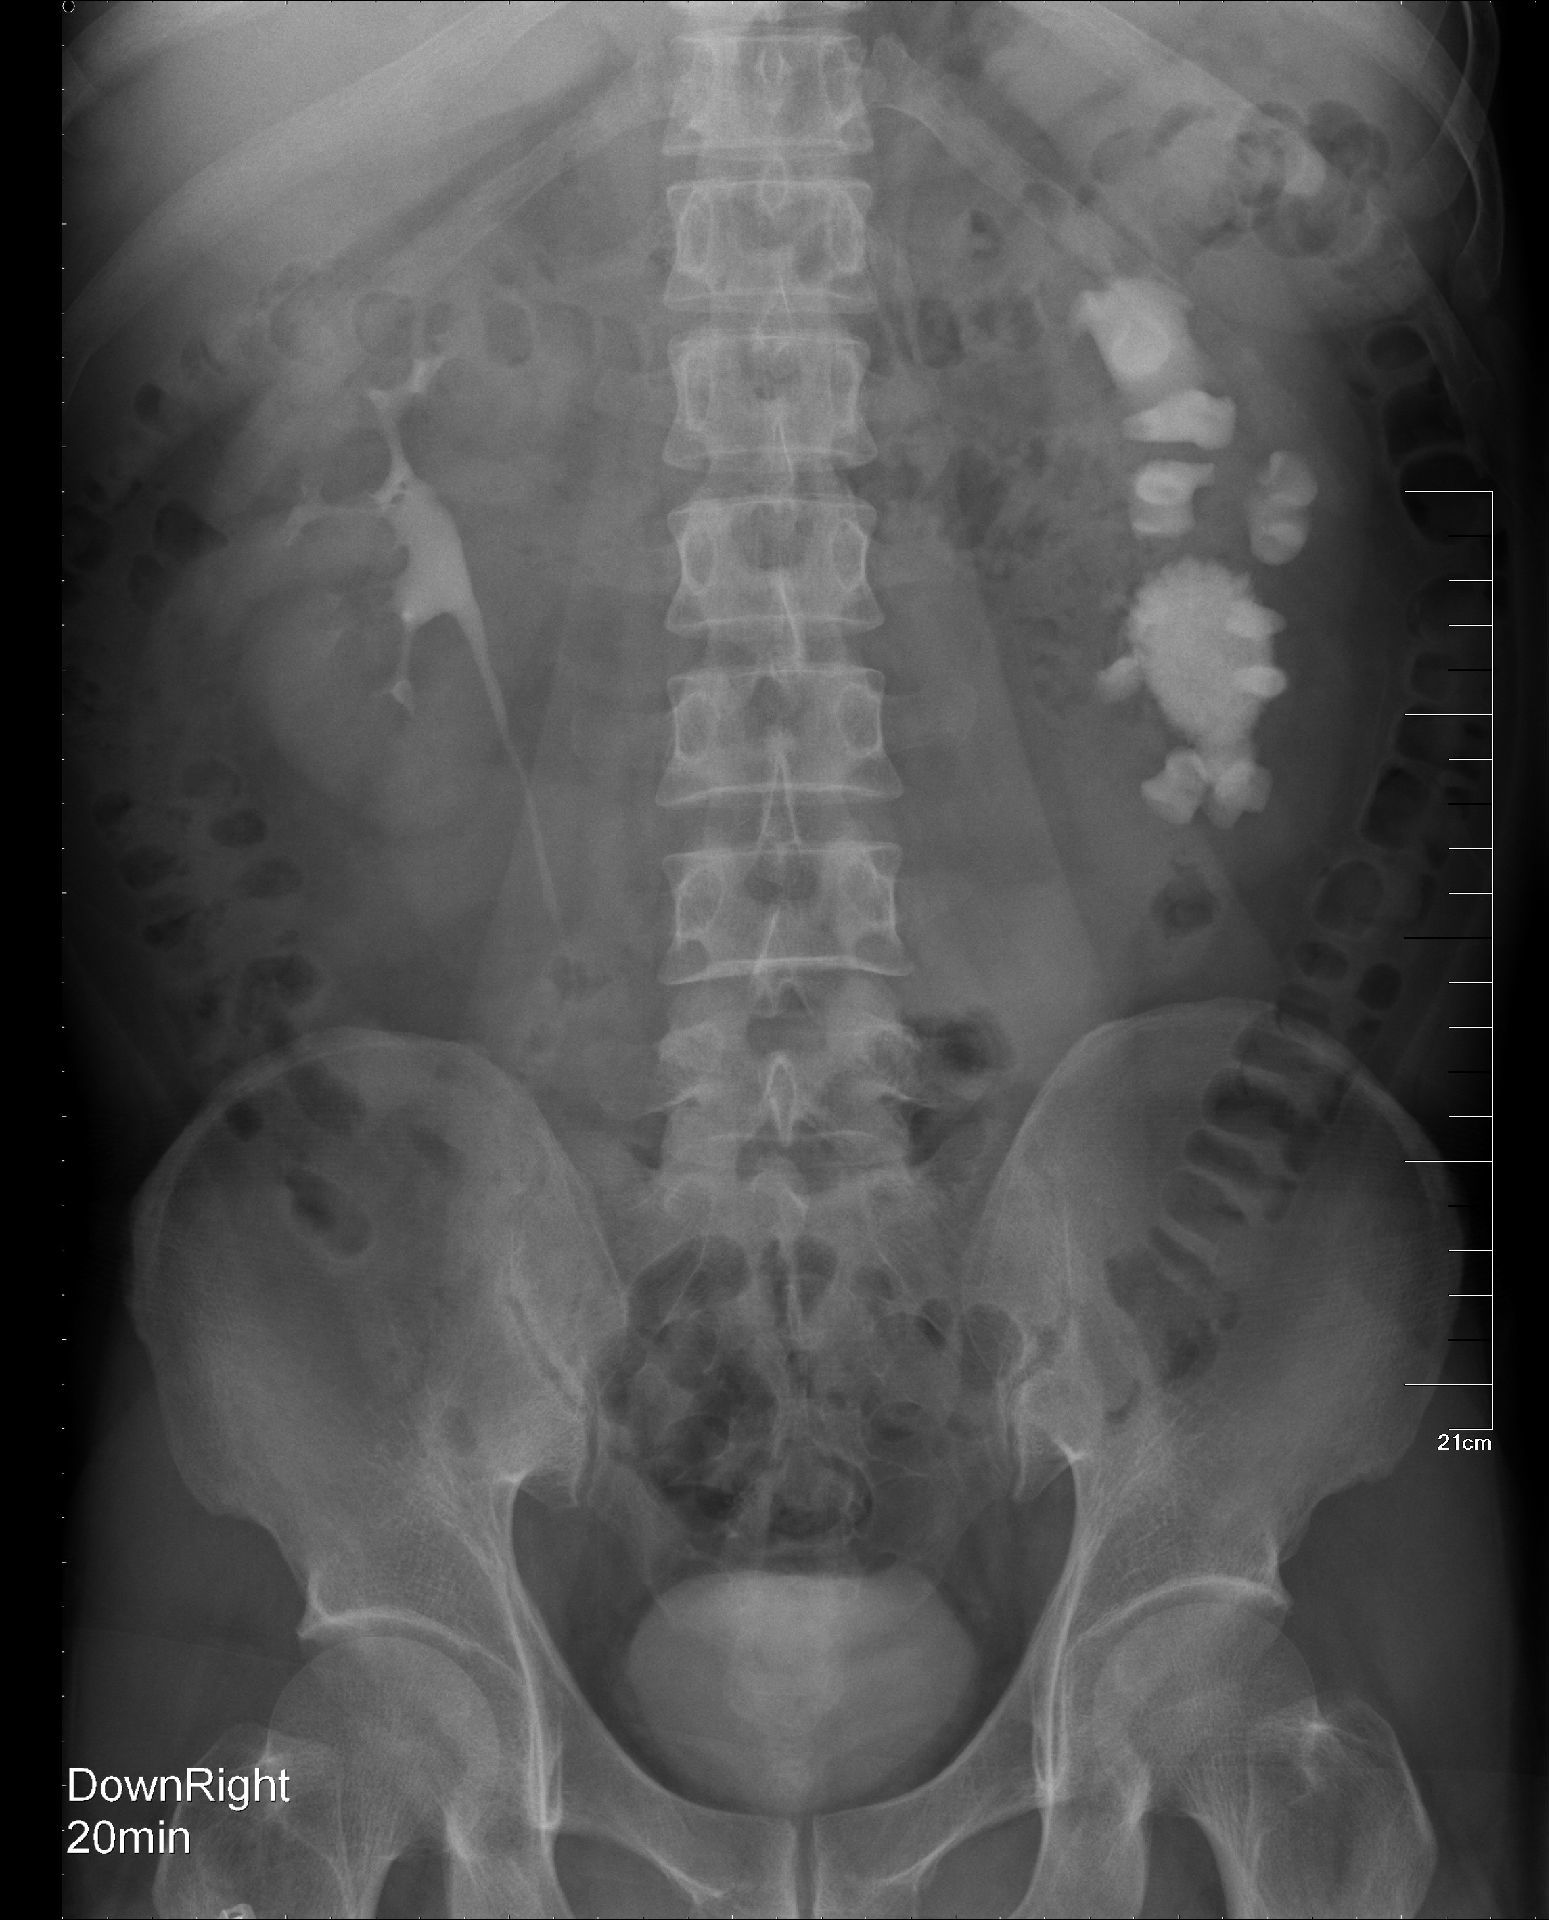

双侧肾盂输尿管重复畸形并肾积水1例

肾盂输尿管重复畸形